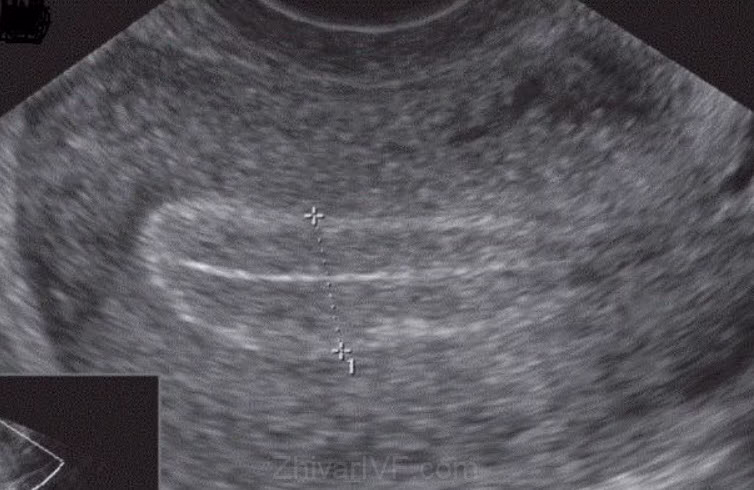

ضخامت مناسب آندومتر رحم در زمان انتقال جنین

از نظر پزشکی ضخامت مطلوب آندومتر در حدود 10 میلی متر بوده و ضخامت کمتر از 7 میلی متر می تواند با کاهش شانس لانه گزینی و بارداری در ART همراه باشد . از این رو ضخامت آندومتر در جریان روش های کمک باروری و دریافت داروها توسط بیمار و با استفاده از سونوگرافی ترانس واژینال بررسی خواهد شد . در این نوع از سونوگرافی از یک پروب ترانس واژینال با فرکانس بالا که از طریق واژن وارد بدن شده و امکان مشاهده دقیق تر ساختارهای لگنی , به ویژه رحم و آندومتر را فراهم می سازد . این تکنیک نسبت به سونوگرافی شکمی , وضوح بالاتری در ارزیابی ضخامت و الگوی آندومتر دارد .

در فرایند انتقال جنین , وجود آندومتر با ضخامت بین ۷ تا ۱۴ میلی متر و برخورداری از الگوی «سه خطی» (Triple-line pattern) به عنوان وضعیت مطلوب در نظر گرفته می شود . در الگوی سه خطی آندومتر در تصویر سونوگرافی ترانس واژینال , دارای یک خط روشن در داخل رحم و دو خط تاریک تر در میانه رحم است (تصویر زیر) . این الگو منعکس کنندهی آندومتری است که در آن لایهی پایه و لایهی عملکردی از یکدیگر جدا شدهاند . علاوه بر اهمیت ضخامت آندومتر در زمان انتقال جنین , این مسئله با میزان تولد به دنبال درمان IVF/ICSI در ارتباط است; به طوریکه میزان تولد در آندومتری با ضخامت کمتر از 5 میلیمتر با کاهش 50 درصدی همراه است .